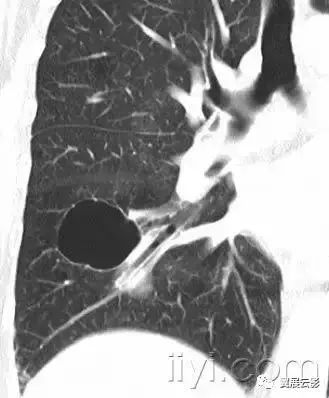

十六、肺大疱:

病理:直径大于25px(通常为几个cm)的含气腔隙,边界清晰,薄壁(小于1mm)。肺大疱常见临近肺的气肿性改变。

平片和CT:肺大疱表现为圆形的局部透亮影或者低密度,直径25px或者更大,薄壁。常可见多发肺大疱及其他肺气肿的表现(小叶中心型和间隔旁型)